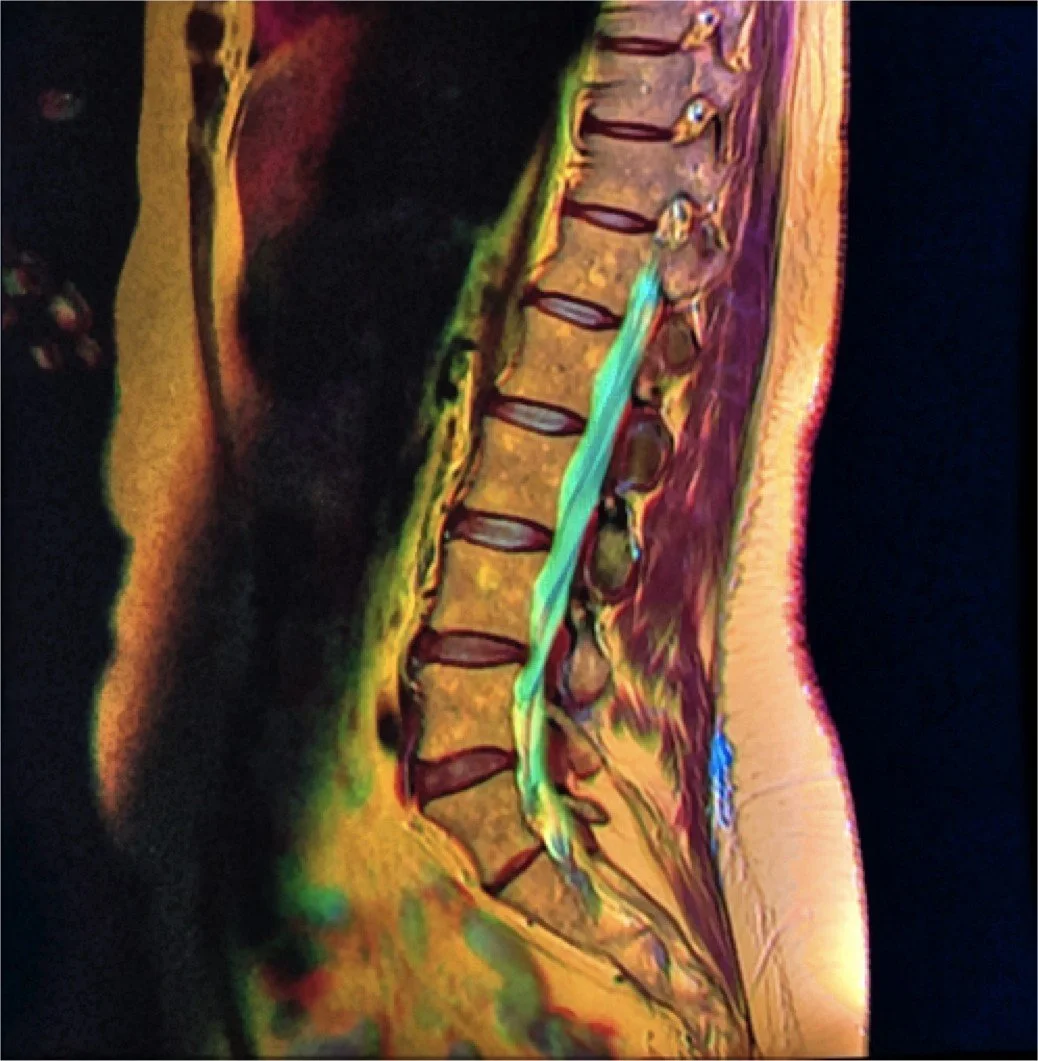

MRI scan of a human spine and lower back.

Spine: Chronic Back Pain, Degenerative Disc Disease